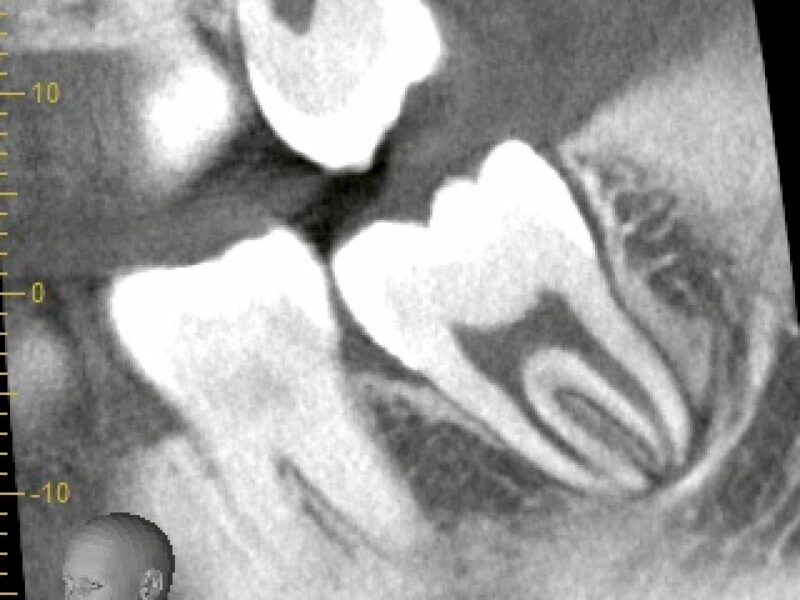

特徴4高精度診断を可能にする「歯科用CT」 -